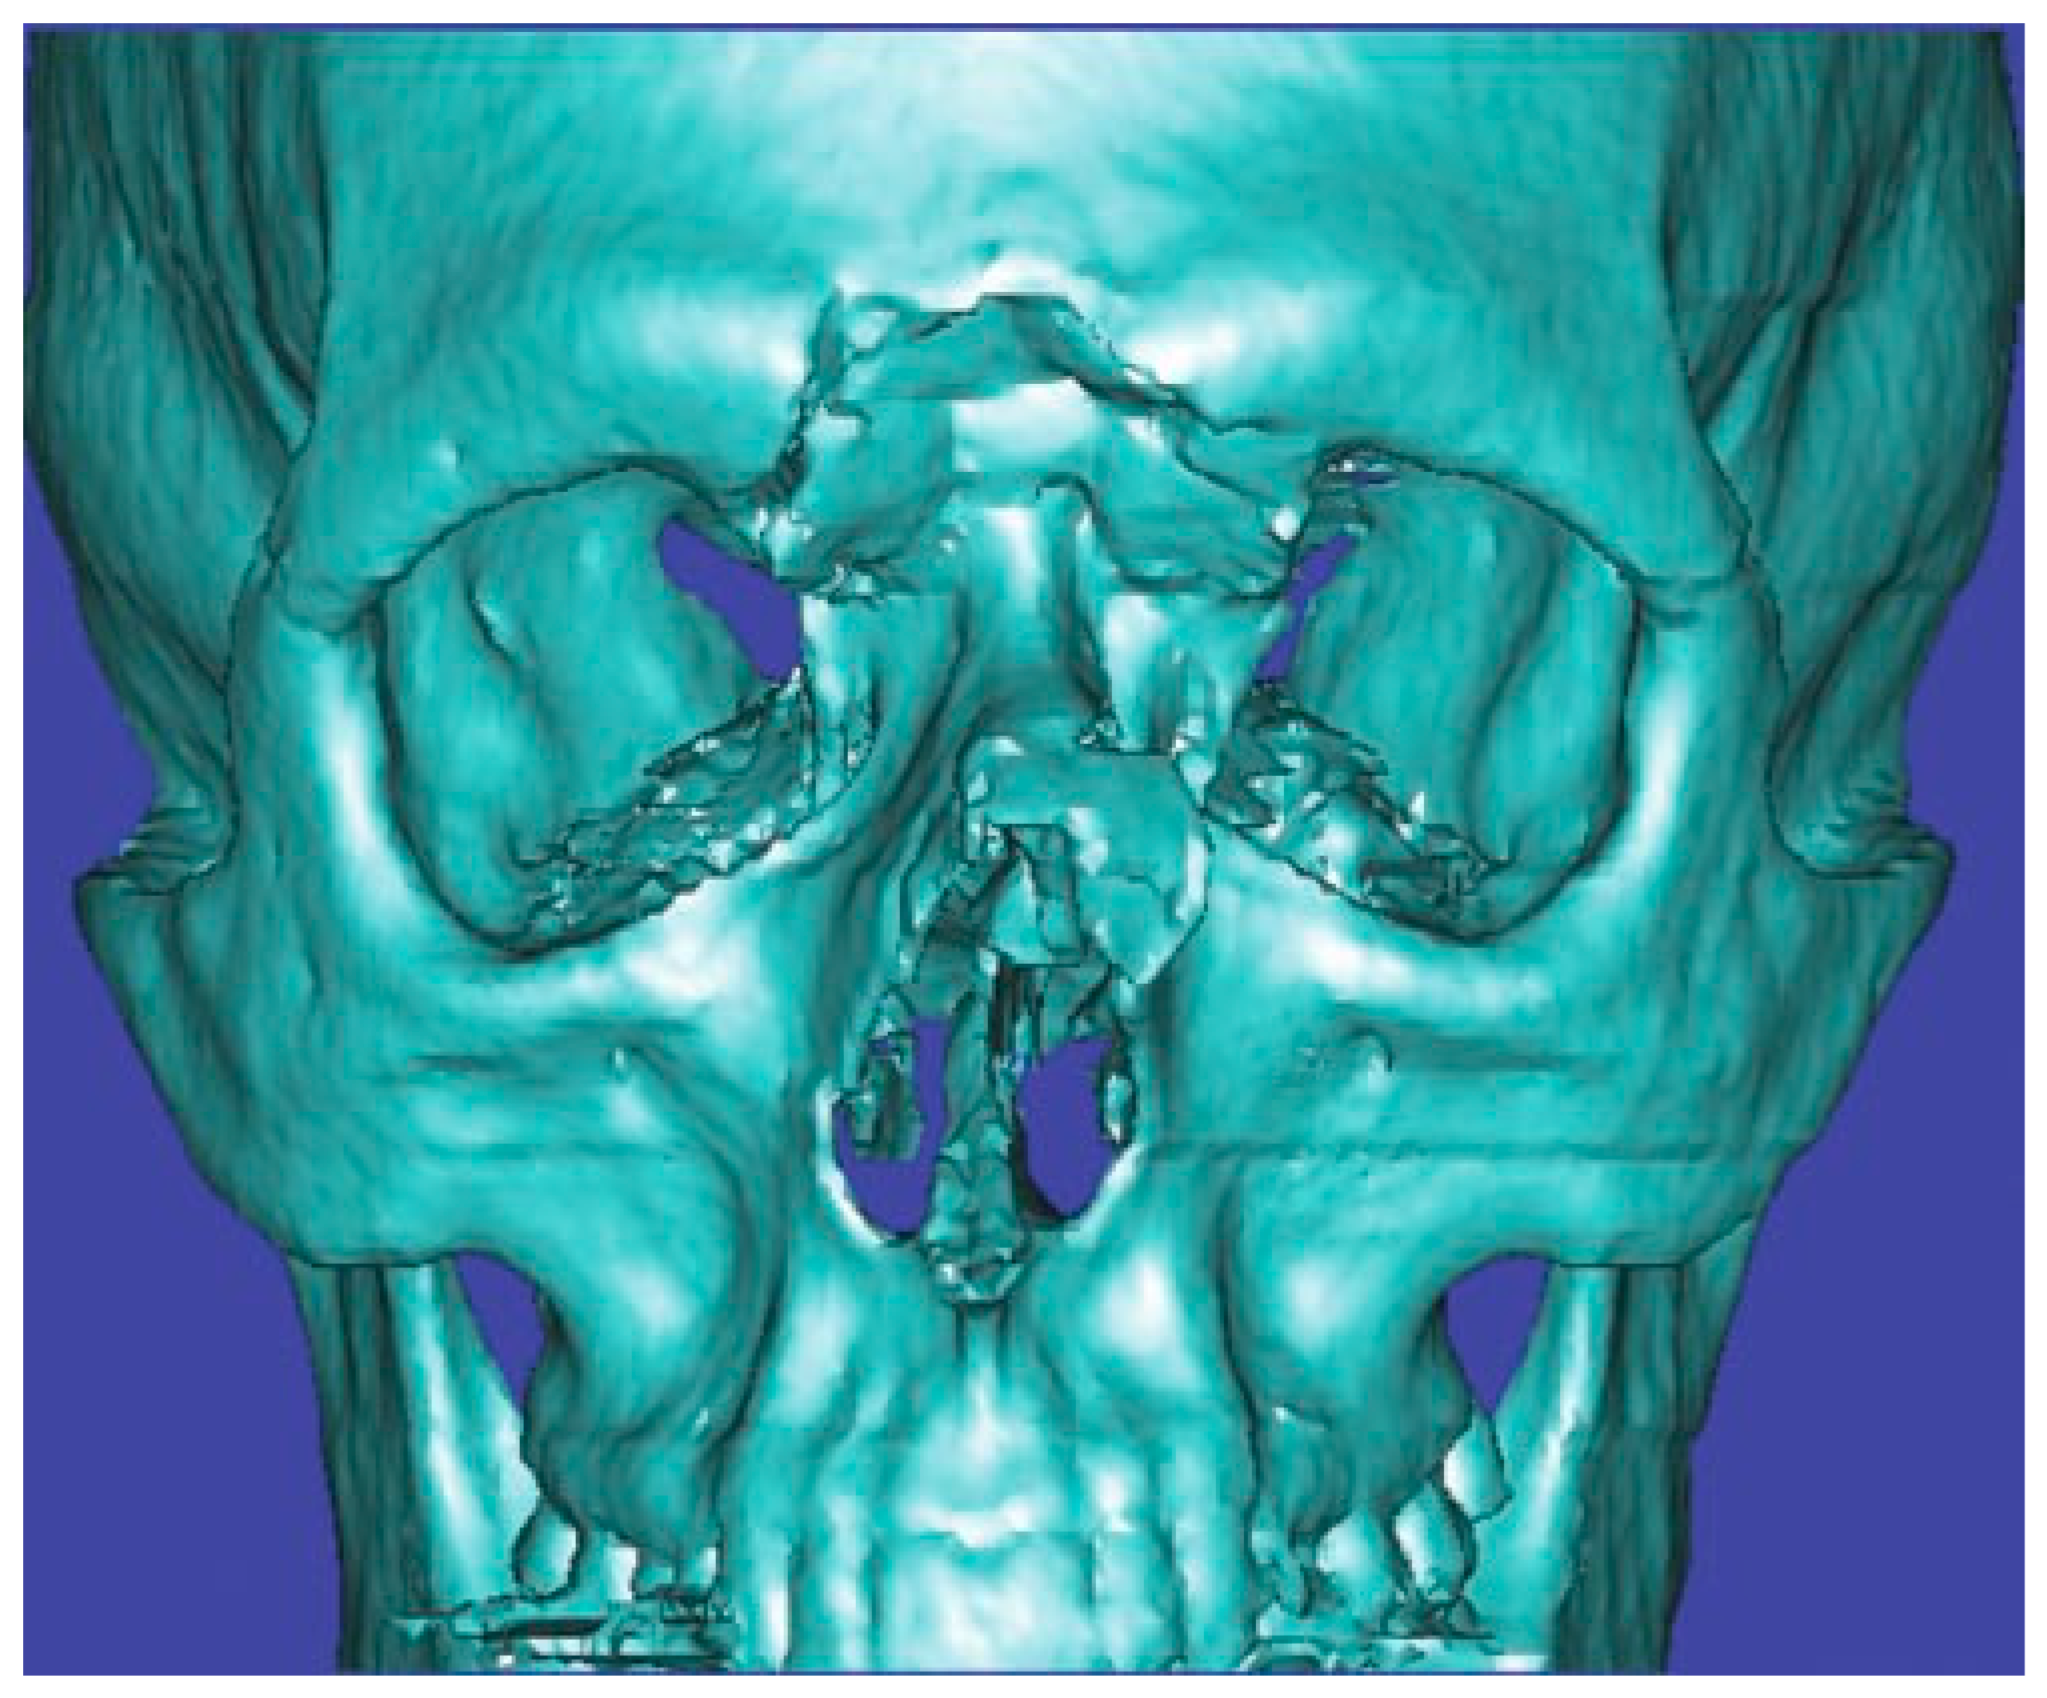

Figure 5.

Three-dimensional computed tomography scan of a frontal sinus fracture. The three-dimensional reconstruction can be helpful in delineating the location of fragments to be located intraoperatively as well as for patient/family education.